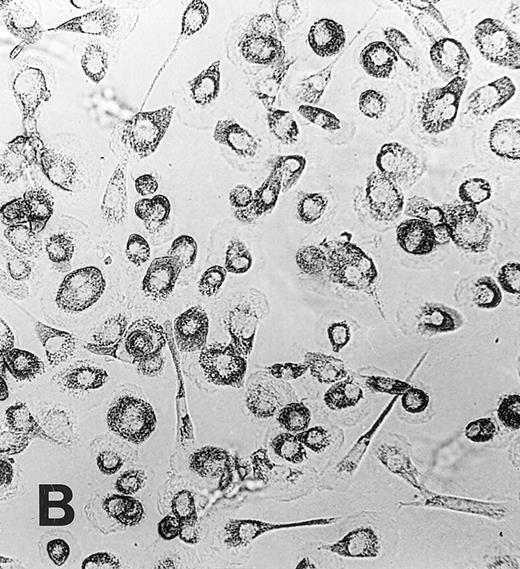

Monocyte to macrophage maturation.During culture in medium Ultradoma-PF supplemented with 10% human serum, monocytes acquired the characteristic morphological features of maturating macrophages, whereas not much change in morphology was observed during culture with medium alone (Fig 1). Viability of freshly isolated monocytes was 98% or more and decreased during 1 week of culture to 85% to 90% (without serum) and 94% to 98% (with serum), respectively. Similar to observations made by others,38 a relatively wide variability was found between different experiments regarding loss of cells in the serum free preparations. Since this did not significantly influence the extent of MGC formation, we made no further attempts to quantify this loss.

Maturation of monocytes into macrophages. Monocytes were cultured in the protein-free medium Ultradoma-PF without (A) or with (B) 10% human serum. In the presence of serum, the cells acquire the typical morphologic features of cultured macrophages. Photographs were taken on day 6 of culture. Giemsa staining, original magnification × 50.

Induction of monocyte fusion and influence of monocyte to macrophage maturation on the formation of MGC.For most experiments, the formation of MGC was induced by stimulation with conditioned medium for 3 days (Fig 3A). With freshly isolated monocytes, fusion rates of up to 90% were obtained. As already noticed previously,37 a relatively wide variation of fusion rates between different donors was observed. In control cultures to which supernatant from unstimulated PBMC had been added for the same time, no MGC formation occurred. When monocytes were stimulated with medium containing FCS and Con A in the same concentrations as in the conditioned medium, isolated MGC were seen in a few experiments, fusion rates being always less than 5%.

(A) MGC derived from freshly isolated monocytes (day 0) stimulated with conditioned medium for 3 days. Giemsa, original magnification × 25. (B) Generation of MGC with PMA and HLA class II MoAb. Monocytes were cultured for 6 days in the presence of 10% human serum before stimulation. Giemsa, original magnification × 25.